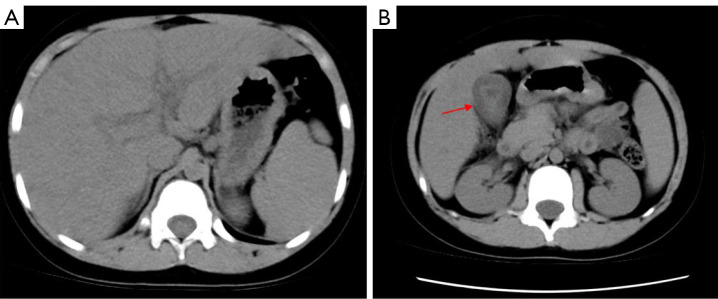

Background: The clinical manifestations of Epstein-Barr virus (EBV) infection are usually infectious mononucleosis, chronic active EBV infection, and related hemophagocytic lymphohistiocytosis. The incidence of non-calculous cholecystitis in children is not high, and non-calculous cholecystitis in children caused by EBV infection remains a rarity, which is often overlooked in clinical practice. The purpose of this study was to describe the clinical characteristics, laboratory tests, imaging findings, and treatment outcomes of a 9-year-old boy.

Case description: This case details a 9-year-old boy who was diagnosed with infectious mononucleosis, acute non-calculous cholecystitis (ACC), and severe hepatic insufficiency. ACC is very rare in pediatric patients, especially because of its own liver function impairment, which is easily overlooked in clinical diagnosis. At the beginning of the disease, the patient presented with upper abdominal pain and vomiting, which was misdiagnosed as acute gastroenteritis, and later with fever, yellowing of the skin, dark yellow urine, repeated abdominal pain and vomiting, and serious liver damage, which was later found to be accompanied by ACC. After receiving regular treatment, the patient's condition improved, with no discomfort reported in the follow-up six months and one year thereafter. This case emphasizes that the clinical work should be carefully performed, in order not to miss any specific clinical manifestations. In this study, we highlight a new problem posed by EBV infection, as well as early awareness of rare cases of ACC in children caused by EBV infection.